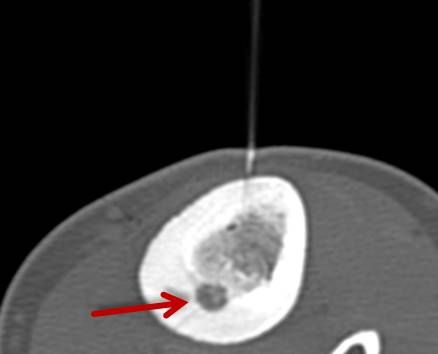

RFA zur Therapie des Osteoidosteoms

Abbildung: Osteoidosteom (Pfeil) im Schienbein bei einem jungen Patienten. Unter CT-Bildgebung wird ein spezieller Applikatoren unter CT-Bildgebung in das Osteoidosteom eingebracht. Durch Hitze wird dieses effektiv und dauerhaft zerstört.